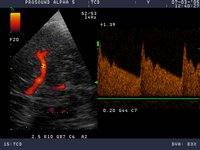

УЗИ СЕРДЦА в МЦ "Качество жизни"

Эхокардиография позволяет с большой точностью распознавать заболевания наружной оболочки сердца — перикарда, хорошо видны утолщения листков перикарда, спайки между ними, наличие жидкости в полости перикарда. Четко выявляются опухоли сердца. Исследование периферических сосудов выявляет, главным образом, сужение их просвета.

Эхокардиография позволяет получать ряд количественных показателей, характеризующих основную функцию сердца. Уже на ранних этапах снижения этой функции можно распознать нарушения и провести соответствующее лечение. Повторные исследования позволяют врачу оценивать эффективность лечебных мероприятий.

Информативность метода и его пределы. УЗИ сердца высокоинформативно (надежность метода достигает 90%) для распознавания пороков сердца. Очень ценные данные дает УЗИ сердца для оценки его функции, благодаря тому, что можно получить количественное выражение очень важных показателей и на ранней стадии выявить признаки сердечной недостаточности.

Стоимость УЗИ сердца 1600р